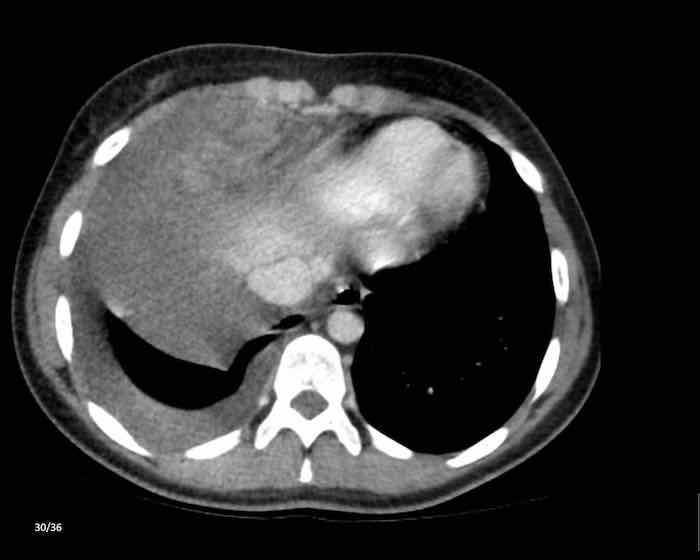

Các hình ảnh này của một nam giới 71 tuổi.

Trên CT ngực, tình cờ phát hiện một khối ở tuyến ức.

Hãy phân tích các hình ảnh. Nhận định của bạn là gì?

Hình ảnh

Một phần tổn thương có ngấm thuốc cản quang và có một số vôi hóa, có thể nằm ở thành nang.

Khi một tổn thương tuyến ức có thành phần đặc, nguyên tắc là… “khi còn nghi ngờ, hãy phẫu thuật cắt bỏ”.

Tổn thương đã được phẫu thuật cắt bỏ dựa trên kết quả CT và kết quả giải phẫu bệnh cho thấy đây là u tuyến ức dạng nang.